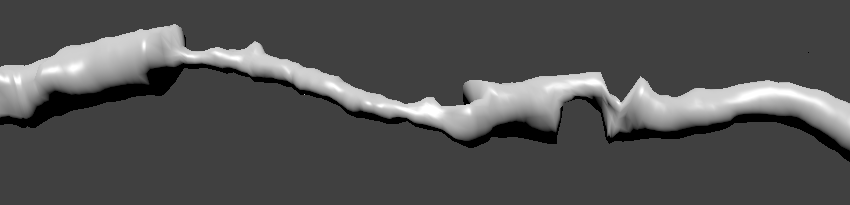

На рисунке ниже изображена трехмерная реконструкция сердца, полученная в результате работы современного томографа:

Для масштаба указана толщина луковицы аорты — 3.2 см, подумать только! Однако, когда у людей возникают проблемы с сердцем из-за сосудов, то речь, как правило, идет вовсе не о таких больших. На изображении видно, что сердце окружено более мелкими сосудами, и некоторые из них ответвляются прямо из крупных артерий. Это так называемые коронарные артерии, которые питают кровью непосредственно сердце. Если в них происходит сужение просвета (стеноз), например, из-за образования кальция, то уменьшается поток крови. Когда стеноз ярко выражен, то случается некроз ткани, другими словами инфаркт. Далее я расскажу о нашем подходе к вычислению границ сосудов, который в результате позволяет автоматически находить сужения и давать им оценку.